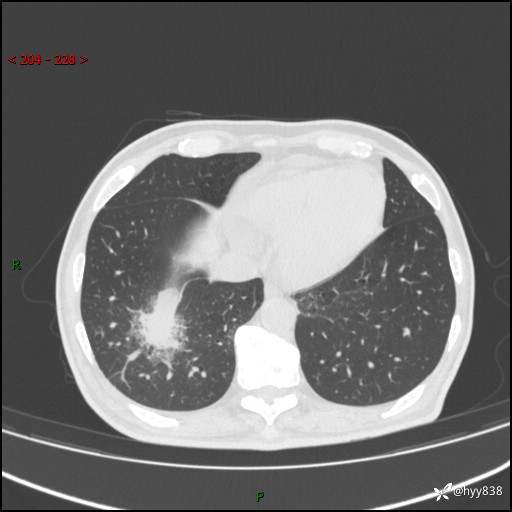

66岁/男,确诊髓系白血病5月,乏力伴气促半月。孤立结节,“晕”的厉害---结果公布~

【患者信息】:66岁/男

【主诉】:确诊髓系白血病5月余,乏力纳差伴气促半月

【现病史及既往史】:患者5月前无明显诱因出现牙龈出血,未重视,2024.5.10社区体检查血常规发现全血细胞减少,后自觉活动后心慌气促,无发热、头痛、咳嗽咳痰、胸痛等,为进一步诊治来我院,门诊以“全血细胞减少”收入,入院后完善相关辅检入院后确诊急性髓系白血病。于2024.06.11给予阿扎胞苷+维奈克拉化疗,给予输血、升白细胞、抗过敏、止血治疗,化疗后粒细胞缺乏,转入层流病房,出现发热,予以抗感染(头孢唑肟、莫西沙星、美罗培南)、抗真菌(卡泊芬净、氟康唑)、利尿、调脂、利胆、护心、护胃、调节免疫(羟氯喹、白芍总苷)、通便、调节胃肠道菌群、营养支持等对症治疗,出院时患者牙龈出血、咳嗽咳痰、腹胀、便秘等不适较前好转,复查血常规提示白细胞计数升高,要求出院,建议继续住院观察,但患者仍要求出院,予以办理。2024-08-06到我院规律化疗,2024-08-08给予阿扎胞苷+维奈克拉化疗,给予输血、升白细胞、抗过敏、止血治疗,化疗后粒细胞缺乏,转入层流病房,出现发热,予以护心、护胃 、营养支持等对症治疗,好转后出院。院外自行停用维纳克拉。半月前患者无明显诱因出现乏力、纳差、活动后气促,无心慌、胸闷,无咳嗽、咳痰,无畏寒、发热等不适,现患者为求进一步诊治来我院,门诊以“急性髓系白血病”收入院。 发病以来,患者精神、饮食欠佳,睡眠一般,大小便如常,体力明显下降,体重无明显减轻。

【检查】:胸部CT平扫